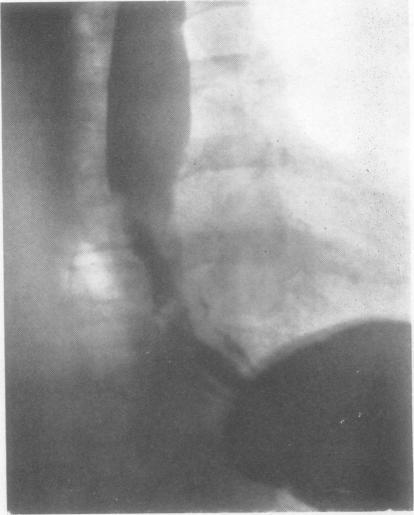

SMITHERS D W

Thorax. 1956 Dec;11(4):257-67. doi: 10.1136/thx.11.4.257.